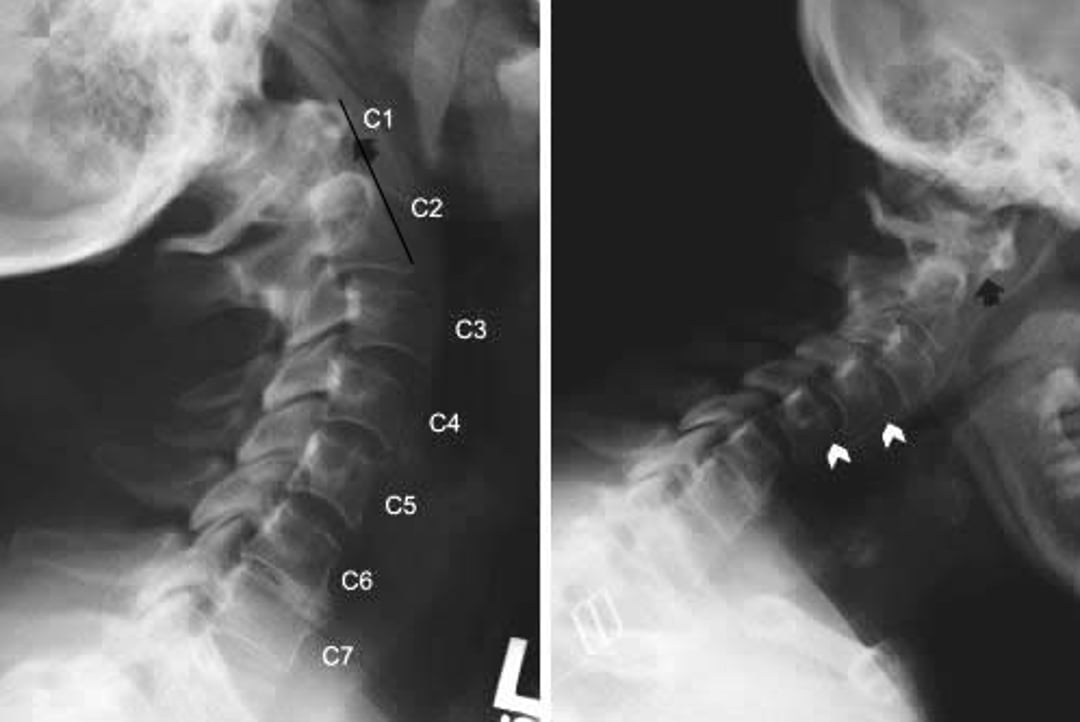

Radiographs of the cervical spine showing atlantoaxial subluxation and subaxial subluxation in a patient with rheumatoid arthritis. The lateral views of the cervical spine were taken in neck extension (on left) and flexion (on right). In flexion, the anterior arch of C1 is far anterior to the dens of C2 (posterior to the black arrow), indicating anterior subluxation. This finding is not evident in extension (black arrow), indicating that atlantoaxial subluxation is dynamic. Anterolisthesis (slipping forward of the upper vertebral body, shown by white arrowheads) is also present at C2-C3 and C3-C4 in extension and at C3-C4 and C4-C5 in flexion.